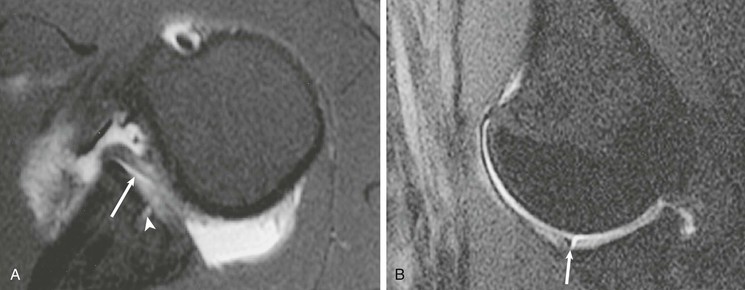

Most cuff tears originate in the supraspinatus tendon; however, large tears may extend into either the infraspinatus or subscapularis tendon. Isolated tears, although less common, occasionally occur in either the infraspinatus or subscapularis (Fig. 44-24) tendon. An isolated tear of the infraspinatus tendon is usually associated with the internal impingement syndrome (discussed further in the section on glenohumeral instability).104 An isolated tear of the subscapularis tendon may result from shoulder dislocation or in association with coracohumeral impingement112 and is best demonstrated on axial MRI as high signal traversing the tendon with retraction of the tendon away from its normal attachment site on the lesser tuberosity. An extension of the subscapularis tendon known as the transverse ligament holds the long head of the biceps tendon in the intertubercular groove, and a tear of the subscapularis tendon may result in disruption of the transverse ligament, leading to medial subluxation or dislocation of the long head of the biceps tendon.113 Axial MRI is well suited not only for evaluating the integrity of the subscapularis tendon but also for demonstrating medial subluxation of the biceps tendon out of the intertubercular groove. The biceps tendon may be displaced superficial to the subscapularis tendon, into the subscapularis tendon (Fig. 44-25) or intraarticular (Fig. 44-26).

A tear of the rotator interval can result from an acute traumatic event or from repetitive microtrauma isolated tears of the rotator interval; they most commonly are diagnosed in conjunction with a tear of the anterior portion of the supraspinatus tendon and/or the upper subscapularis tendon. Disruption of the rotator interval can result in shoulder pain and allow superior migration of the humeral head (microinstability). MRI findings of an isolated rotator interval tear include a high T2-weighted signal isolated to the rotator interval or disruption of the capsule of the rotator interval.124 Direct MRA improves detection of the disrupted capsule at the level of the interval and may actually demonstrate leakage of contrast material through a defect into the subacromial-subdeltoid bursa or extension of contrast to the posterior surface of the coracoid process as reported by Vinson et al.124 (Fig. 44-30). Schaeffeler et al.126 recommended caudal or anterior displacement of the biceps tendon because they are more sensitive than previously proposed criteria for pulley lesions.